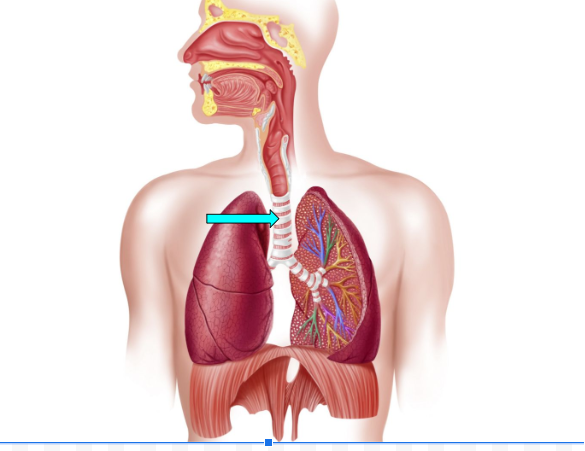

Bronchus (pic)

Bronchi

carry oxygen to and from the lungs